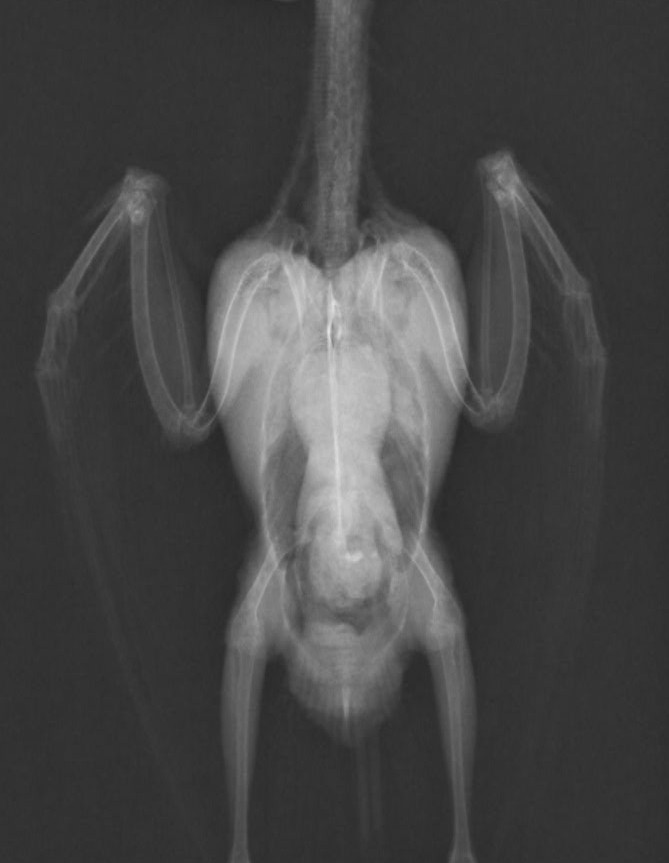

症例:2か月例 性別不明 オカメインコ

今朝から呼吸がおかしいとの主訴で来院。来院時、努力性呼吸で酸素化を行ったが短時間で亡くなってしまいました。

原因の究明のため検案を行いまして、左の肺の主気管支に膿がたまっておりまして、それが死因であるとしました。

膿瘍の大きさは1㎝にも満たない大きさでした。こんな小さなものでここまで重篤な症状が出てしまいます。鳥を飼育の方に置かれましては毎日の体重測定と呼吸状態の確認をお願いしております。